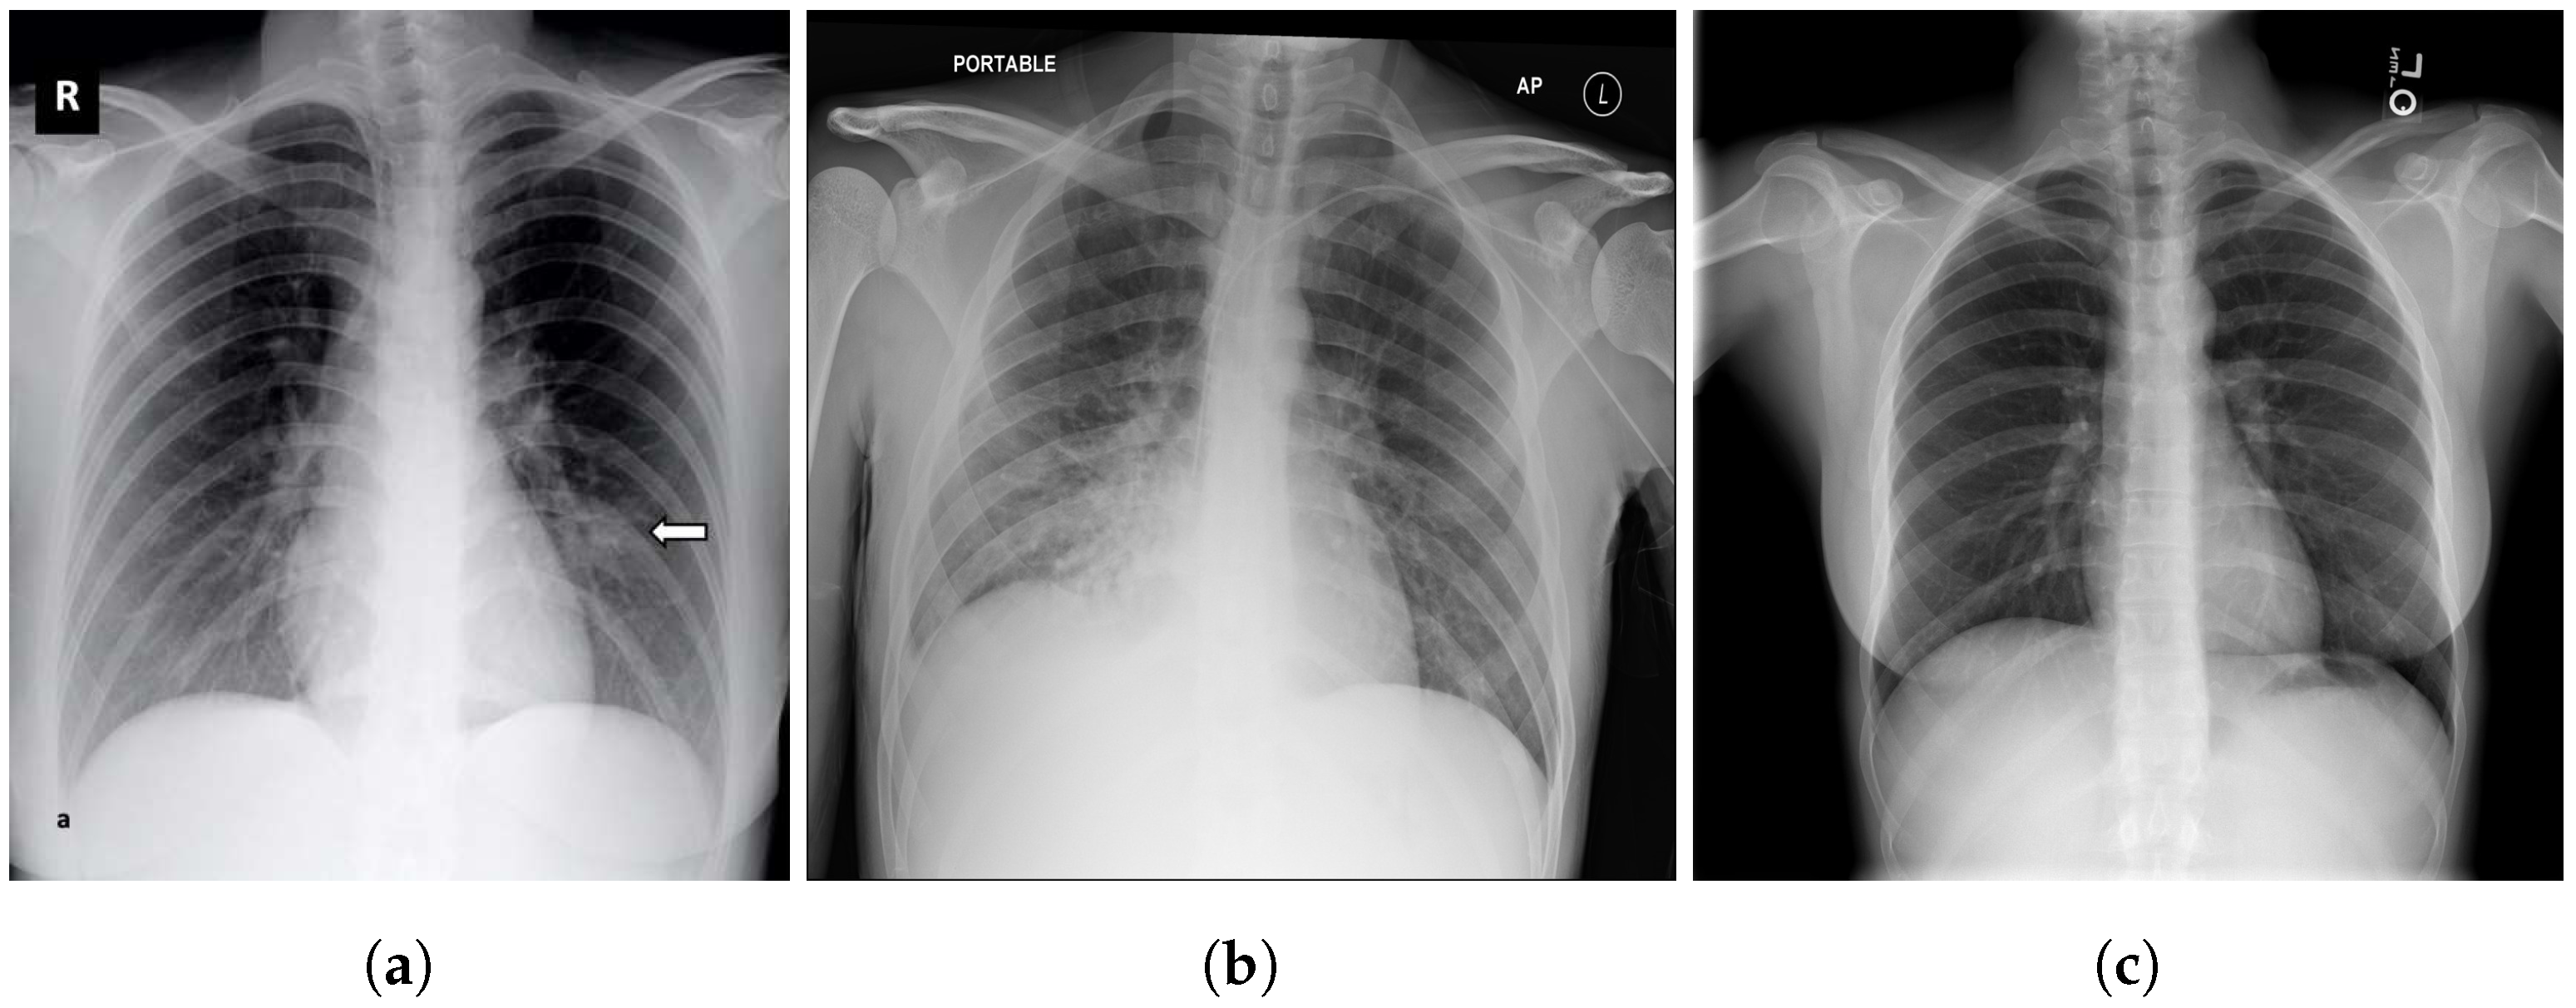

3.4. RSNA

3.5. Chest X-ray Images Pneumonia (CXRIP)

3.6. Montgomery County X-ray

3.7. Shenzhen Hospital X-ray